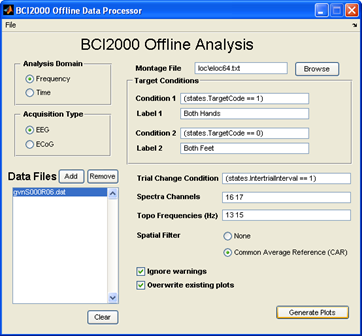

ESM的局限性激发了一种互补的映射技术,该技术基于对行为任务期间ECoG或立体EEG被动记录的功率谱(特别是在高频)中与任务相关的变化的估计。这种映射技术,以下简称ECoG功能映射,生成与任务相关的皮层激活地图,其中可能包括任务招募但对任务性能不重要的皮层。相比之下,ESM使用皮层功能的暂时电生理破坏来模拟组织切除的急性行为影响,并被认为特定于对任务表现至关重要的区域。尽管如此,一些临床研究表明,ECoG功能映射和ESM之间存在良好的对应关系。此外,几项研究表明,ECoG功能映射可用于预测切除后的神经损伤,在某些情况下,它预测了ESM没有预测的损伤。由于这些原因,一些癫痫手术中心已经开始使用ECoG功能映射作为ESM的补充,有时提供皮层功能的初步地图,以指导ESM的使用。然而,由于缺乏技术资源,特别是可用于临床脑电图监测系统的软件,大多数癫痫中心尚未采用ECoG功能映射。近年来开发了几个ECoG功能映射包。例如,SIGFRIED在校准块中获得了神经活动的大量基线分布,然后通过平均行为在时间块中引发的神经活动来快速积累皮层激活的估计值。一种名为cortiQ的商业产品能够执行这种基于块的映射范式,这使得训练有素的临床专业人员能够进行被动ECoG映射。(SIGFRIED和cortiQ都是使用BCI2000框架构建的)